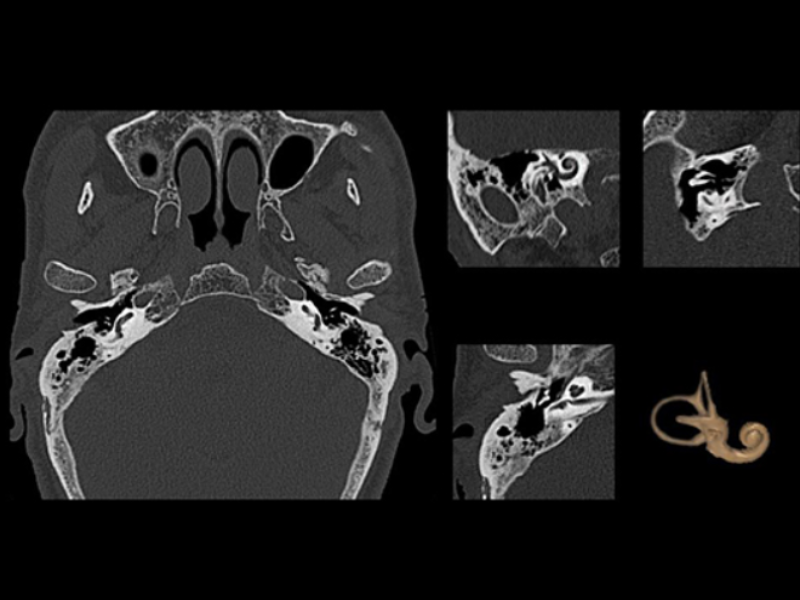

Ossicles and Inner Ear